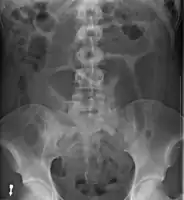

- Abdominal x-ray – tire-like shadow arising from right iliac fossa and passing to left

Plain X ray of a cecal volvulus -